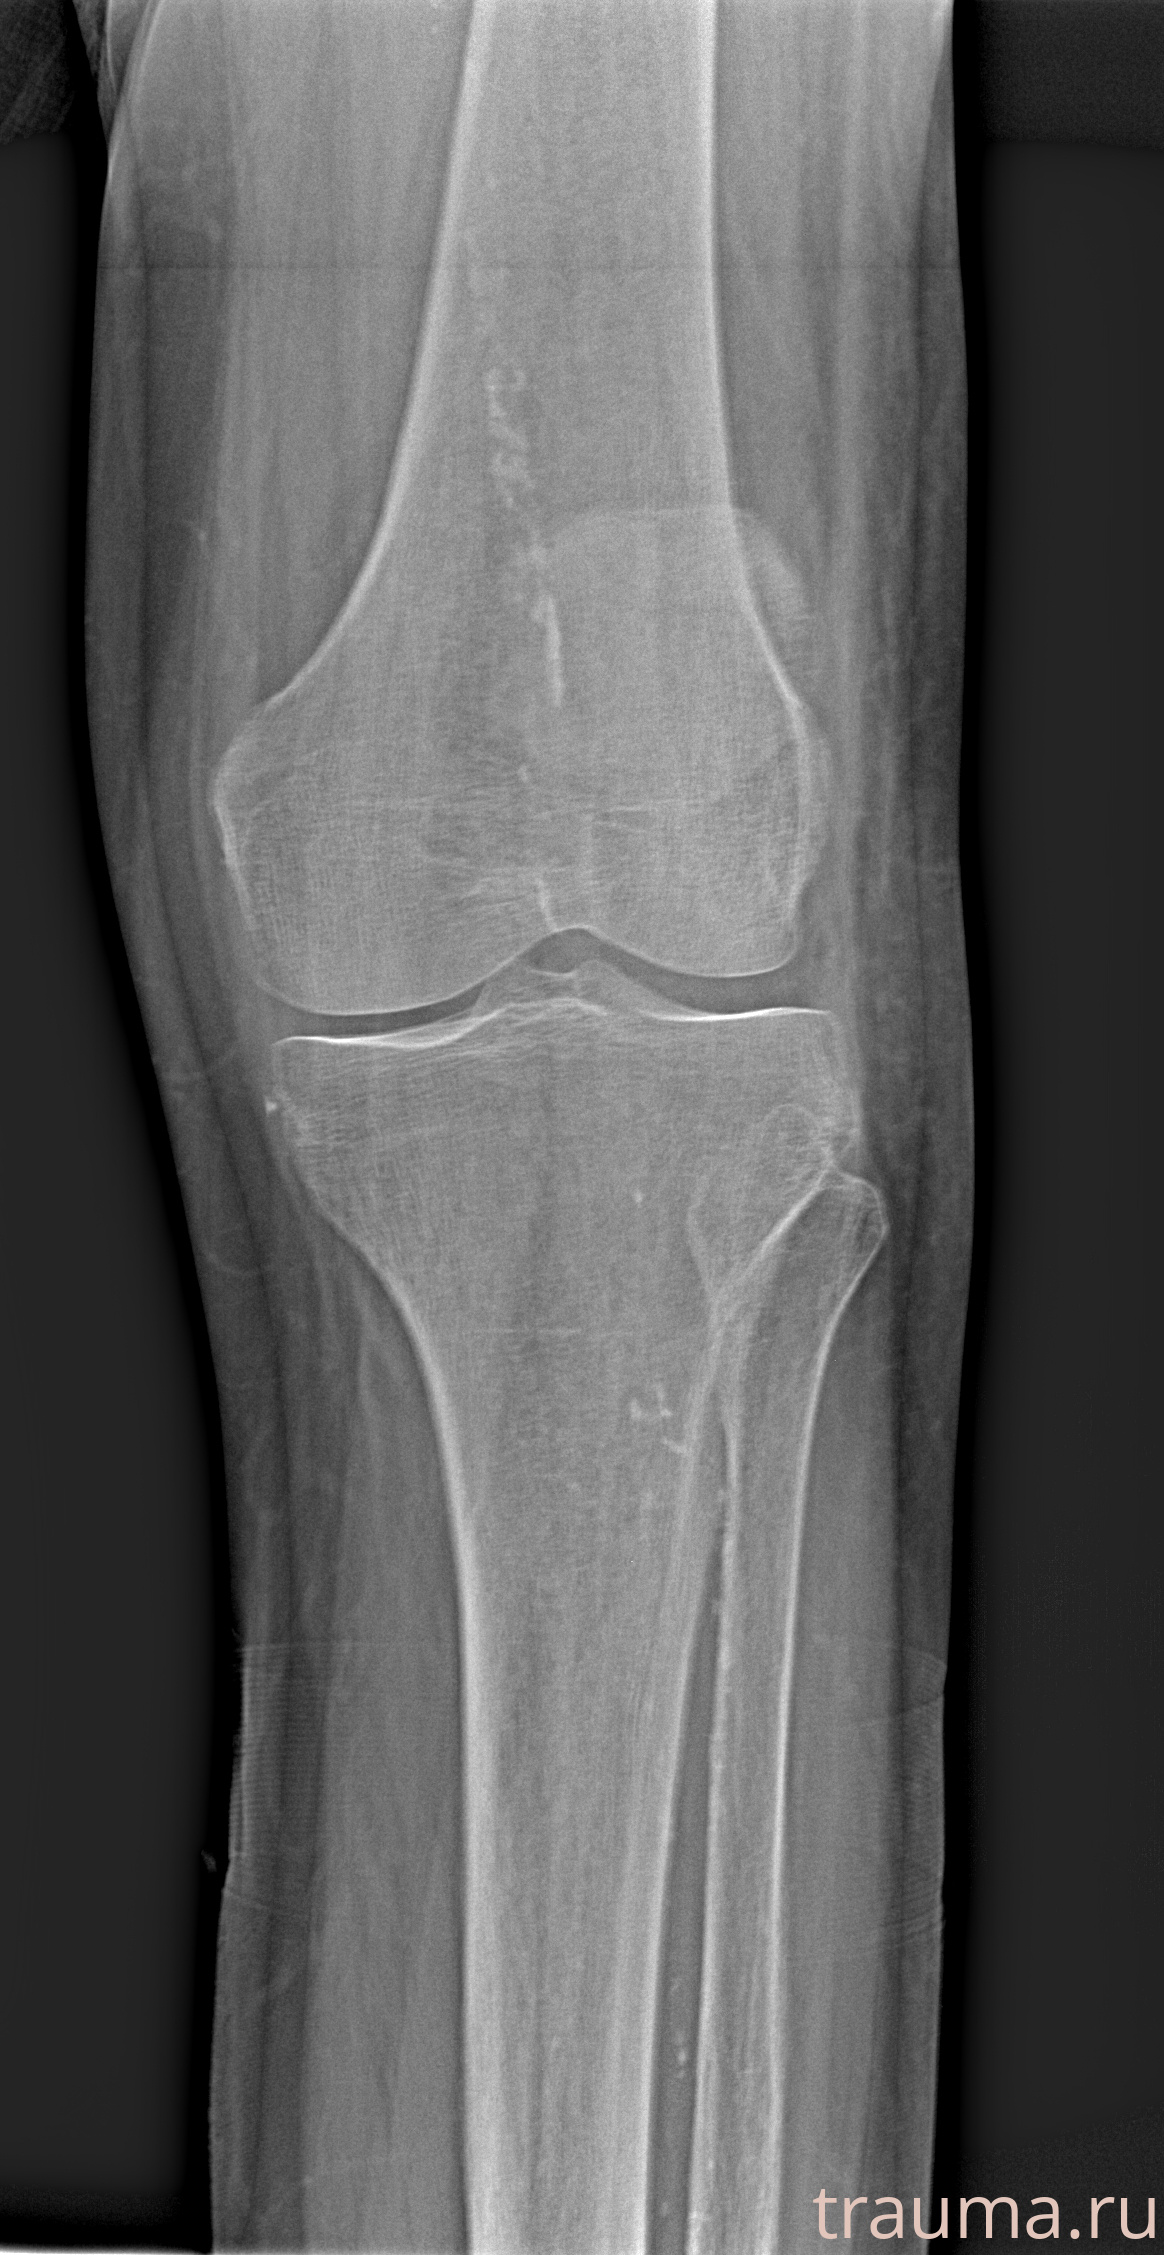

Рентгенограммы

Рентген на дому: по вашему адресу приезжает врач-рентгенолог, травматолог-ортопед с мобильным рентгеновским аппаратом, проводит диагностику травмы или заболевания, делает необходимые рентгенограммы, дает рекомендации по дальнейшему лечению. Получить качественные снимки в домашних условиях возможно благодаря уникальной методике, разработанной МосРентген Центром для института  Склифосовского